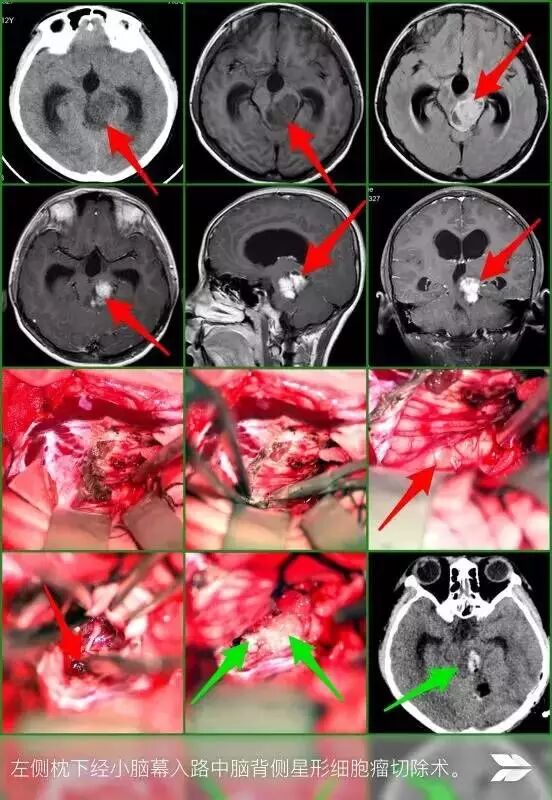

入院后,根据小杰的病情,立即完善相关术前检查后,张永力院长带领杨海洋医生及二病区相关医护人员,针对小杰病情进行了充分的手术风险评估,终决定尽快在全身麻醉下行 “左侧枕下经小脑幕入路中脑背侧胶质瘤切除术”。手术按期进行,根据小杰病情特点,术前给予放置腰大池引流管,开颅术前适当释放脑脊液降低颅压,便于术中操作,术中见肿瘤呈灰白色,质地软,由于肿瘤主体位于中脑背侧,和周围神经血管粘连紧密,且血供丰富,切除十分困难,经过细心的分离,在显微镜下,双极电凝及术中超声吸引器配合下,镜下肿瘤全切,手术顺利完成。术后病理诊断为少突胶质细胞瘤,小杰术后各项生命体征正常,正在恢复中,可正常饮食和下床行走,目前拟出院。

据张永力院长介绍,脑胶质瘤约占颅内肿瘤的46%,是颅内肿瘤中发病率高的,可发生于颅内任何部位,成人多见于大脑半球,青少年及儿童常见于脑干。脑干胶质瘤占儿童神经系统肿瘤的10%~20%,平均发病年龄为5~9岁,多于出现颅高压及颅神经损伤症状后就诊。对脑干胶质瘤的治疗目前主要是放射治疗、手术治疗、化疗,目前对脑干胶质瘤的治疗方法,不同学者有一定的争议,主张个体化治疗原则。该例患者肿瘤位于中脑背侧,采取手术治疗,手术的目的为解除脑干的压迫、恢复脑脊液循环的通畅及明确肿瘤性质,争取在不增加神经功能损伤的情况下,尽可能显微镜下多切除肿瘤,拟术后辅以放化疗。术中进行脑干神经功能监测,显微镜下利用超声吸引器(CUSA)切除肿瘤,切除效果满意,患者恢复良好,无明显脑干神经功能损伤症状。